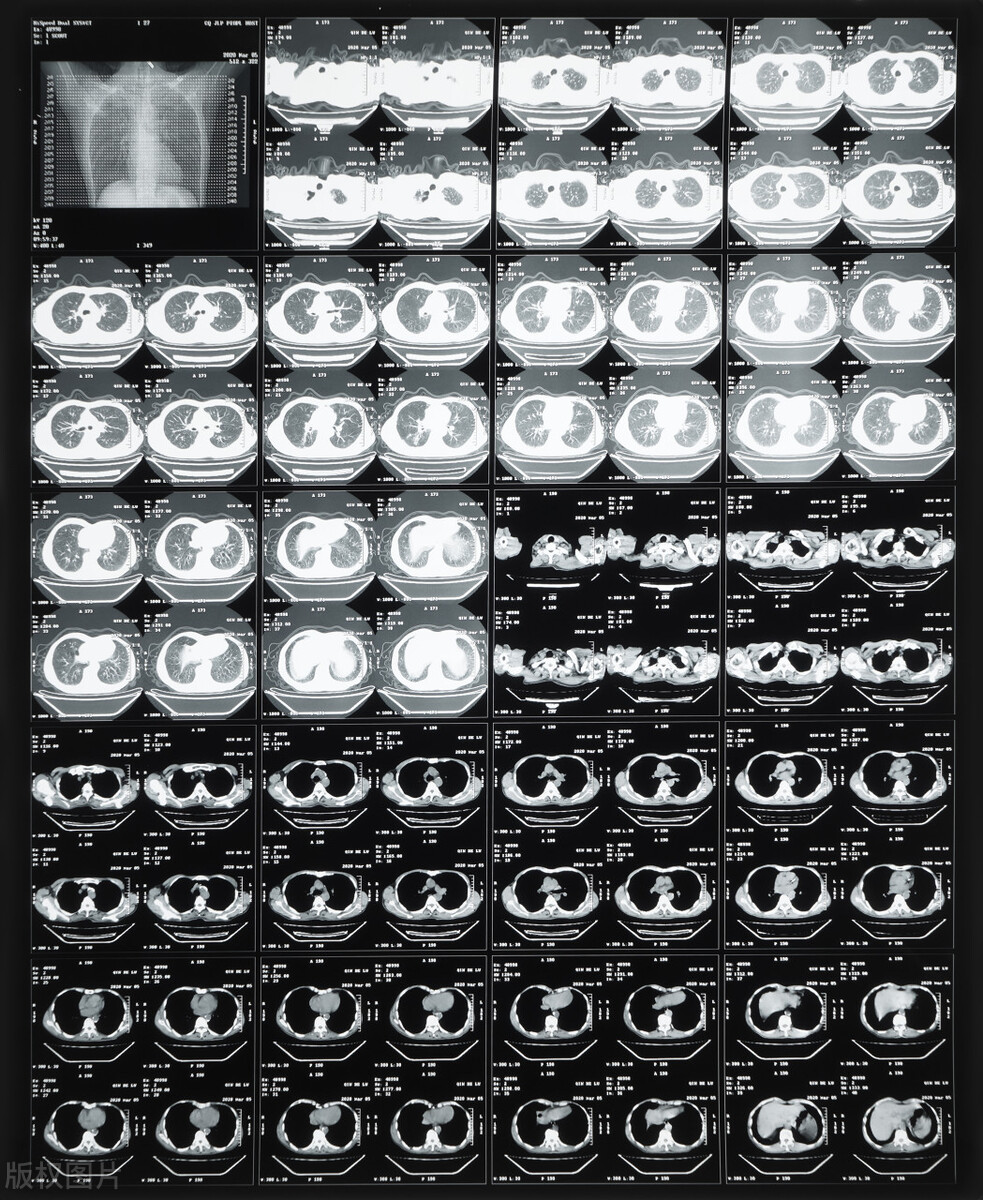

图中为CT片子,可以全面清晰的看到病变

答案是肯定的,恢复状态一般看你的状态和基础血液等指标,还需要看你的病变有没有变小、吸收,这个时候就只能通过胸部CT看到里面了。